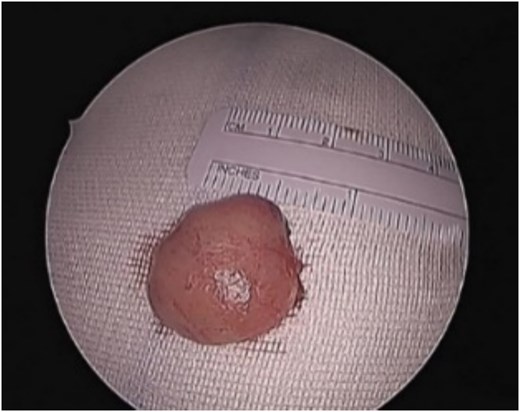

Patient underwent endonasal endoscopic excision of the left nasal septal tumor (Fig. 2). The postoperative recovery of the patient was uneventful. The immunohistochemical examination showed that the tumor cells were positive for CD34 and CD99 while negative for smooth muscle Actin, Desmin, and S100. The final histopathological examination confirmed the diagnosis of a solitary fibrous tumor of the nasal of septum. The patient remained symptoms free with no recurrence on regular follow-ups for 2 years.

Sinonasal SFTs are usually slow growing tumors presenting as painless mass. Alobid et al. reported 21 cases of SNT SFTs. Most common clinical presentations were unilateral mass, rhinorrhea, nasal obstruction, epistaxis, and/or exophthalmos. Anosmia, epiphora, visual disturbance, facial pain and headache can also be present [10]. Our patient presented with painful unilateral mass associated with nasal obstruction and rhinorrhea. As per reported cases in literature, tumor sizes ranged between 1.7 and 8.5 cm [11]. Excised SFTs were described by the authors as well-encapsulated fibrous masses with rich vascularization that were white, reddish or pinkish, oval or round in shape [11].